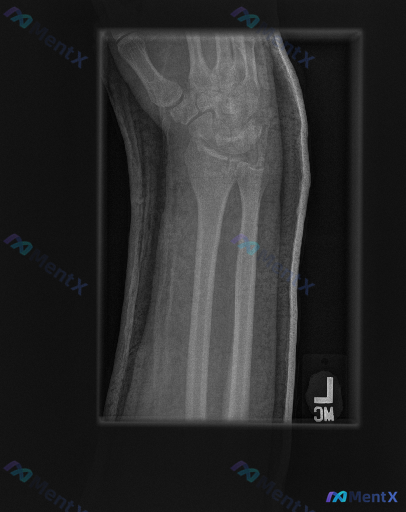

整理到一份左前臂及腕部侧位X光片的影像资料,先和大家同步客观所见的线索: 1. 骨骼方面:桡骨远端背侧和掌侧皮质有连续性中断,可见骨折线涉及关节面,断端有背侧移位、背侧成角的表现,局部有粉碎或压缩改变;尺骨远端(尺骨茎突)处也可见透亮线。 2. 关节方面:桡腕关节的对应关系有改变,随桡骨移位出现背侧...